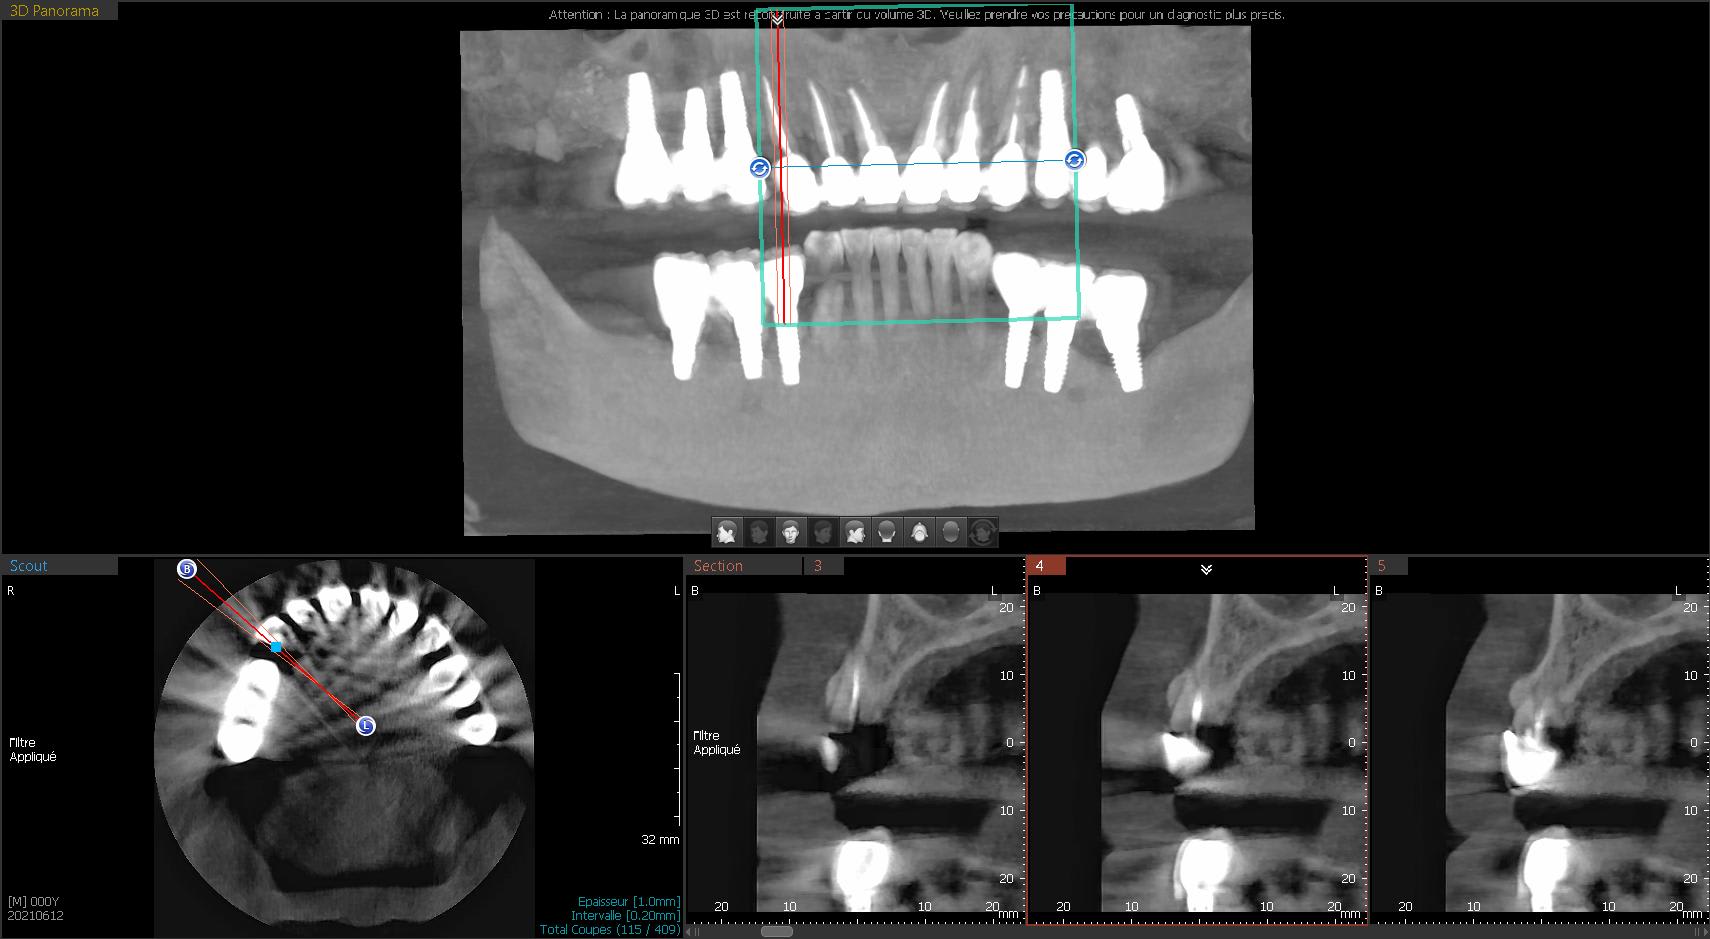

je vais entamer ma première MCEI de 13 à 23 .

J'ai choisi comme schéma la pose en 13 12 22 23 , en 11 et 21 la présence du paquet vasculonerveux palatin antérieur me refroidit.

4)forage le plus palatin possible et le plus apicalement (idealement du 13 mm)

5)mise en place des implants 22 12 13 23 à 40 N

juste faire attention à l'axe du forage: ne pas se faire piéger par l'alvéole.

22 et 23 ont clairement des pêches, c’est une contrindication pour une implantation immédiate, alors pour une mci, encore plus.

Je n’ai pas tout le scan, mais en 11 et 21, je ne vois pas vraiment le problème. Je ne comble pas mes extractions, je ne vois pas l’interêt.